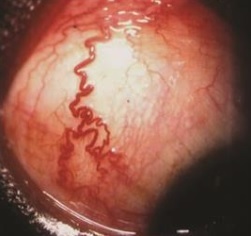

“arterialized” episcleral vessels.

Carotid cavernous fistula

cavernous sinus thrombosis

venous malformations

scleritis with vortex vein blockade